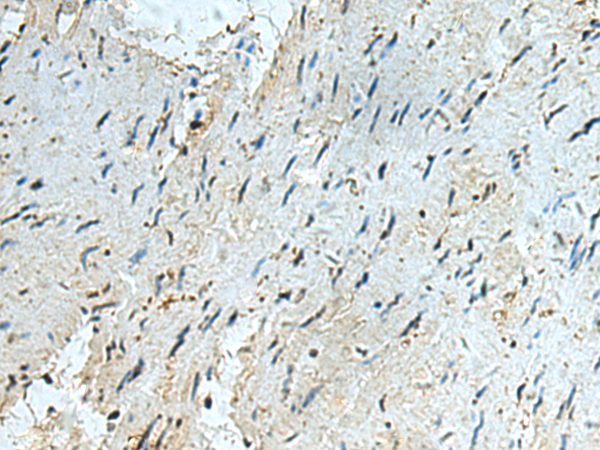

分类: 科研抗体货号: P03354别名: ICF45; IHG-1; hTHG1应用: IHC反应种属: Human, Mouse, Rat